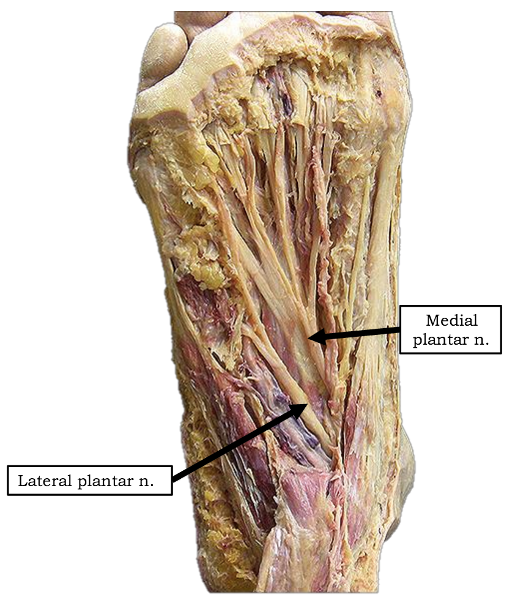

Into which nerves does tibial nerve bifurcate?

medial and lateral plantar nerve

Which muscles are innervated by the medial plantar nerve?

abductor hallucis and flexor digitorum brevis

1 medial lumbrical

flexor hallucis brevis

Which muscles are innervated by lateral plantar nerve in the first layer of dorsal surface?

abductor digiti minimi

origin and distribution of lateral plantar nerve

O tibial nerve beneath flexor retinaculum

D abductor digiti minimi muscle (foot), flexor digiti minimi brevis muscle (foot), quadratus plantae, 3 lateral lumbricals of the foot, adductor hallucis muscle, plantar interossei muscles, dorsal interossei muscles

origin and distribution of medial plantar nerve

O tibial nerve beneath flexor retinaculum

D abductor hallucis, the flexor digitorum brevis, the flexor hallucis brevis, and the first lumbrical

branches of lateral plantar nerve

deep branch

superficial branch

branches of medial plantar n

common plantar digital nerves --> proper plantar digital nerves